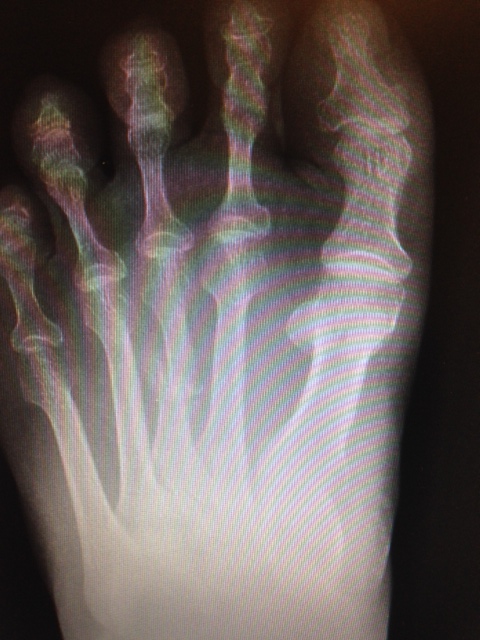

In general, metatarsals are roughly shaped like the chicken bone in a drumstick, with a long shaft and an outward expansion on either end. Fractures can occur at either the head of the bone, the neck, the shaft, or the base. The location of the fracture depends on where the force is being applied. There can also be variability in the shape of the fracture. Some fractures go across the bone in a straight line, others veer off at an angle. The fracture may be in several pieces, or may be completely crushed. Movement can sometimes occur where one of the fracture pieces shifts up, down, or to one side of its natural alignment. It is also possible for the fracture to be incomplete and only pass through part of the bone. Stress fractures can also occur, in which a microscopic fracture occurs slowly as a result of chronic stress, and not so much an immediate injury.

Metatarsal fractures are common foot injuries that are painful, and often under treated by emergency rooms that initially diagnose them. The metatarsals are the long bones of the foot that extend from the middle of the foot to the toe bases. There are five of them, corresponding with the five toes. The most common fractures of these bones involve the second through fourth metatarsals. The first metatarsal, corresponding with the big toe, is far less commonly fractured due to its size and stability, and when it is fractured this is usually related to a concurrent dislocation of the more than one metatarsal in the middle of the foot. The fifth metatarsal, corresponding with the little toe, can have fractures similar to the second through fourth metatarsal, although it also has more unique fracture patterns that can develop at its base. The uniqueness of these fractures, known as a Jones fracture and a styloid avulsion fracture, are due to the increased mobility this bone has over the other metatarsals, leading to more instability.